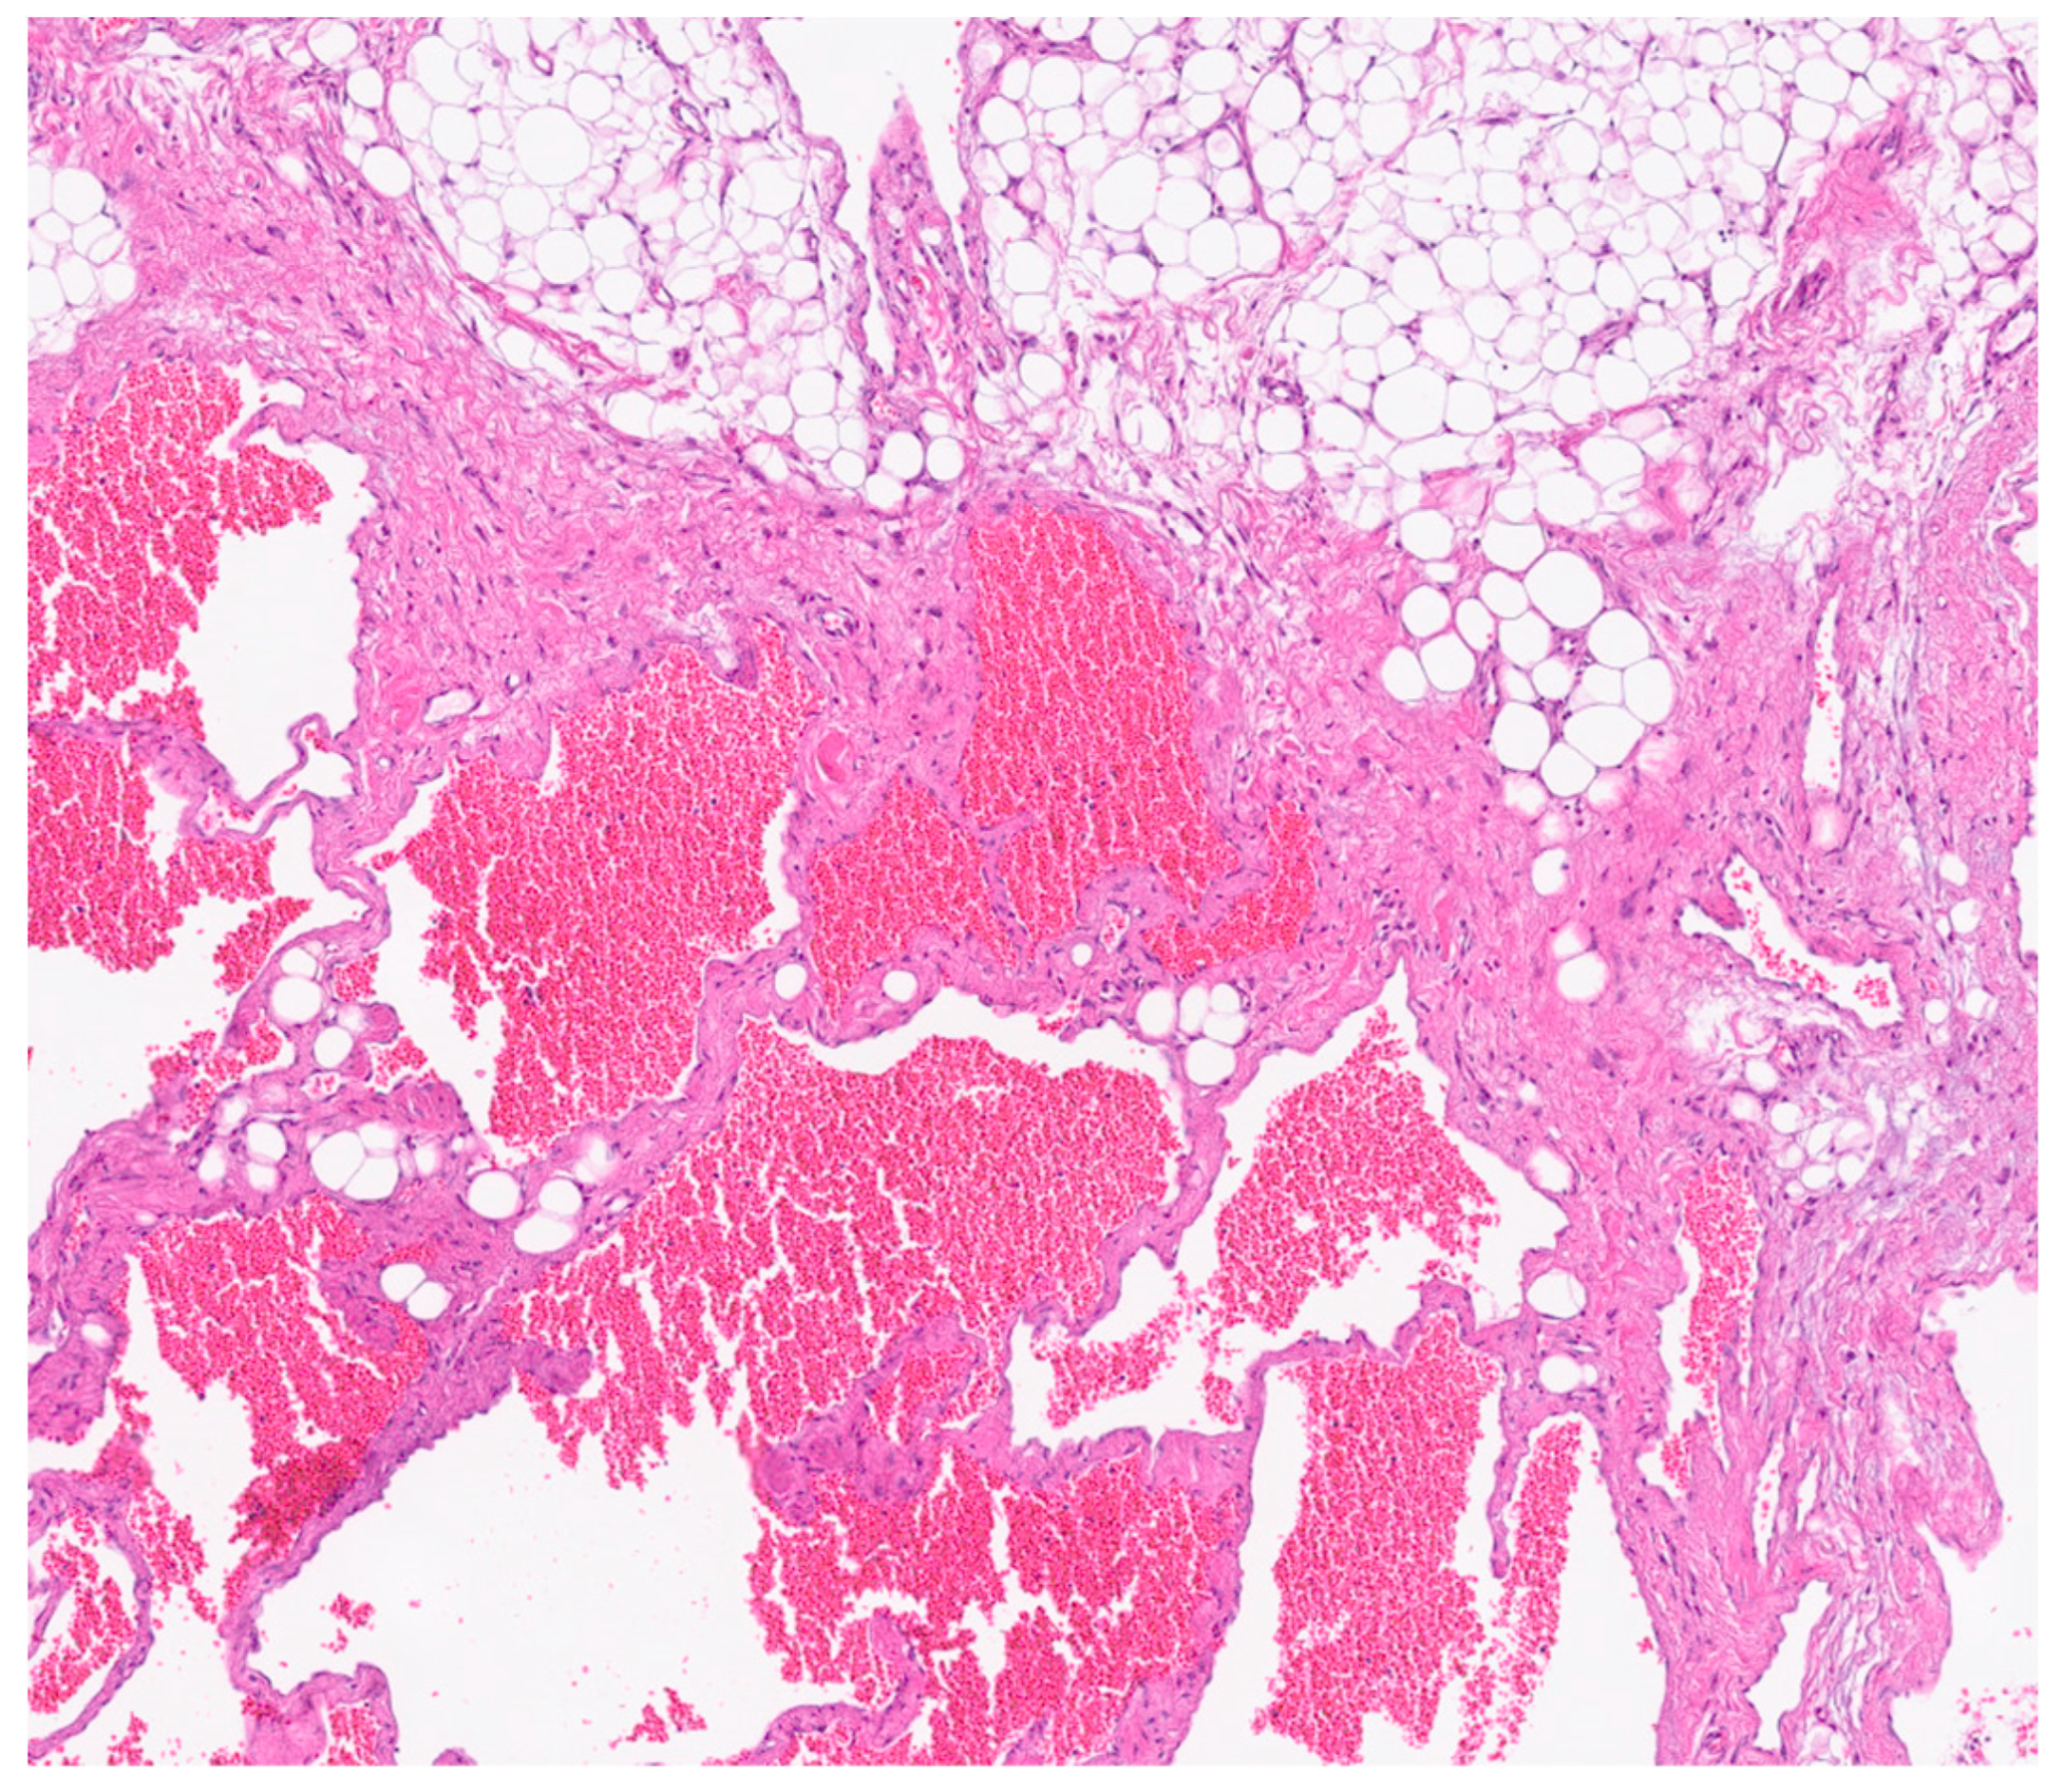

Figure 6. H&E stained section shows the lesion is composed of variably sized anastomosing vascular spaces.

Immunohistochemical analysis revealed strong positivity for CD31, CD34, and podoplanin (D2-40), highlighting the coexistence of venous and lymphatic endothelial components [5]. This supported the final histological diagnosis of a combined lymphatic-venous malformation, in accordance with the 2018 ISSVA classification [4] (Figure 6 and Figure 7).

Histological analysis revealed fibroadipose tissue containing smooth muscle elements and blood vessels, without significant cellular atypia. Cytological examination showed amorphous material, occasional pigment-laden macrophages, a moderate number of granulocytes, and a small fragment of fibroadipose tissue with sparse lymphocytic infiltration.